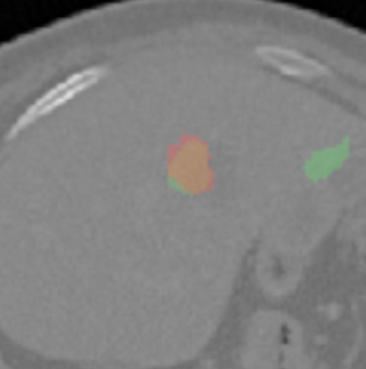

Each pixel of the image is assigned to one of the two classes liver/other tissue and tumor/other tissue, respectively, with a certain probability. Results of the automated liver and tumor segmentation are visualized in Figure 3.2. Comparison with ground truth and segmented liver and tumor give rise to the assumption that our approach is highly promising for obtaining high performance metrics. To qualitatively evaluate performance, we applied some of the commonly used evaluation metrics in semantic image segmentation. Performance metrics are summarized in Table 1.

We evaluate this model under usage of test and validation set from LiTS-Challenge and Innsbruck data ( images). The evaluation metrics are summarized in Table 1. The liver segmentation evaluation scores indicate that our models, especially perform remarkable good, provided that the sequential approach outperforms the One-Step method primarily in the tumor segmentation task. in Pixel accuracy, Intersection over union (IoU) and Rand Index (RI) have values very close to . IoU and Rand Index performance score of the tumor segmentation show that the application of balanced loss with , achieves the best results.